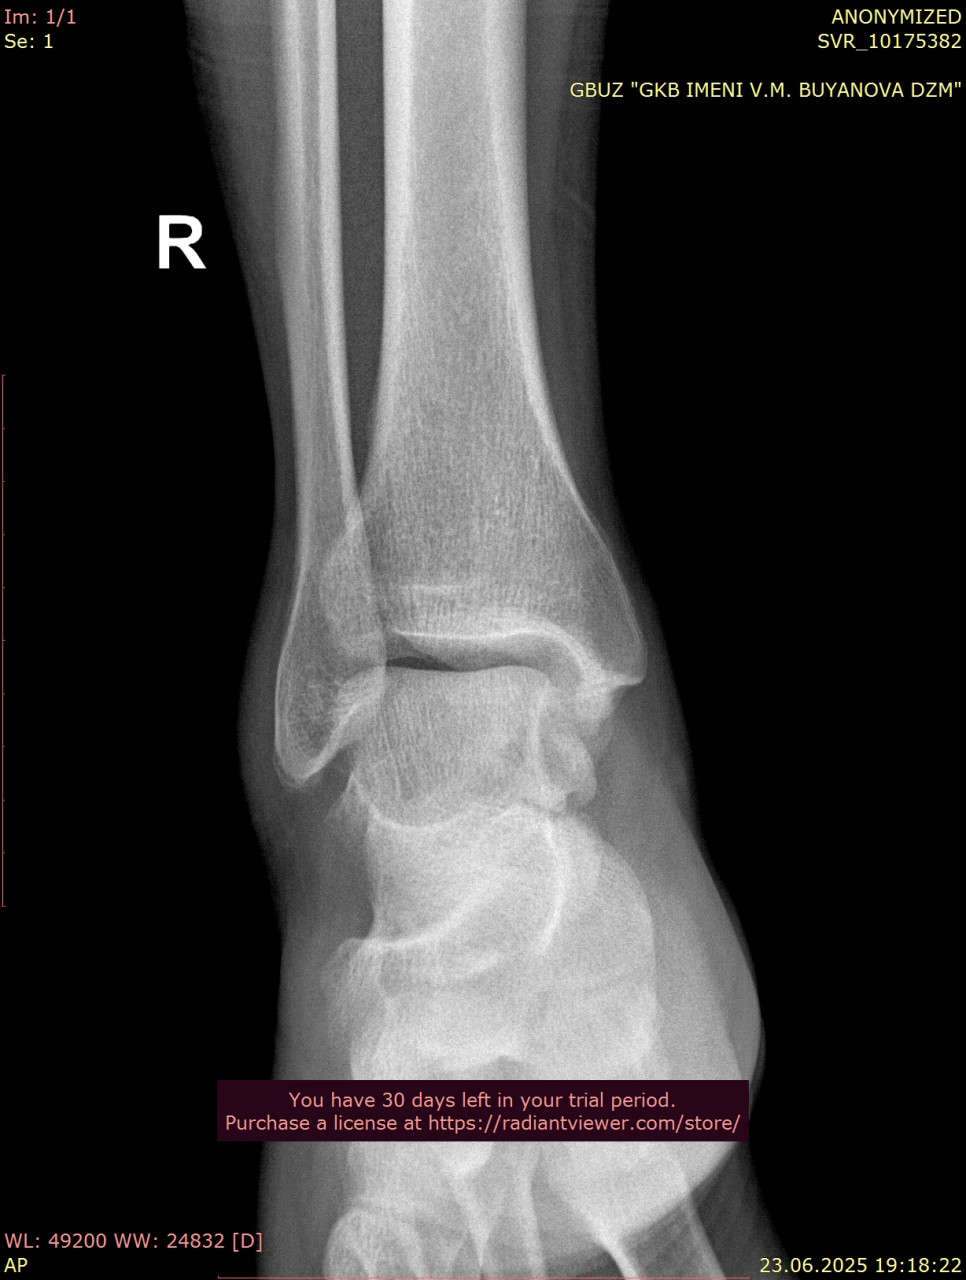

Посмотрите, пожалуйста, снимки голеностопного сустава от 23.06.2025, когда был перелом, и спустя почти 11 недель от 04.09.2025. Переломы срослись нормально? нужно ли делать еще один рентген в будущем? От 23.06.2025 прикрепляю только одну проекцию из за лимита сайта.

Здравствуйте. По вашим снимкам костная мозоль сформировалась, перелом срастается удовлетворительно, признаков смещения нет. Дополнительный рентген обычно не требуется, если нет боли или отёка, но окончательное решение принимает лечащий травматолог при очном осмотре.